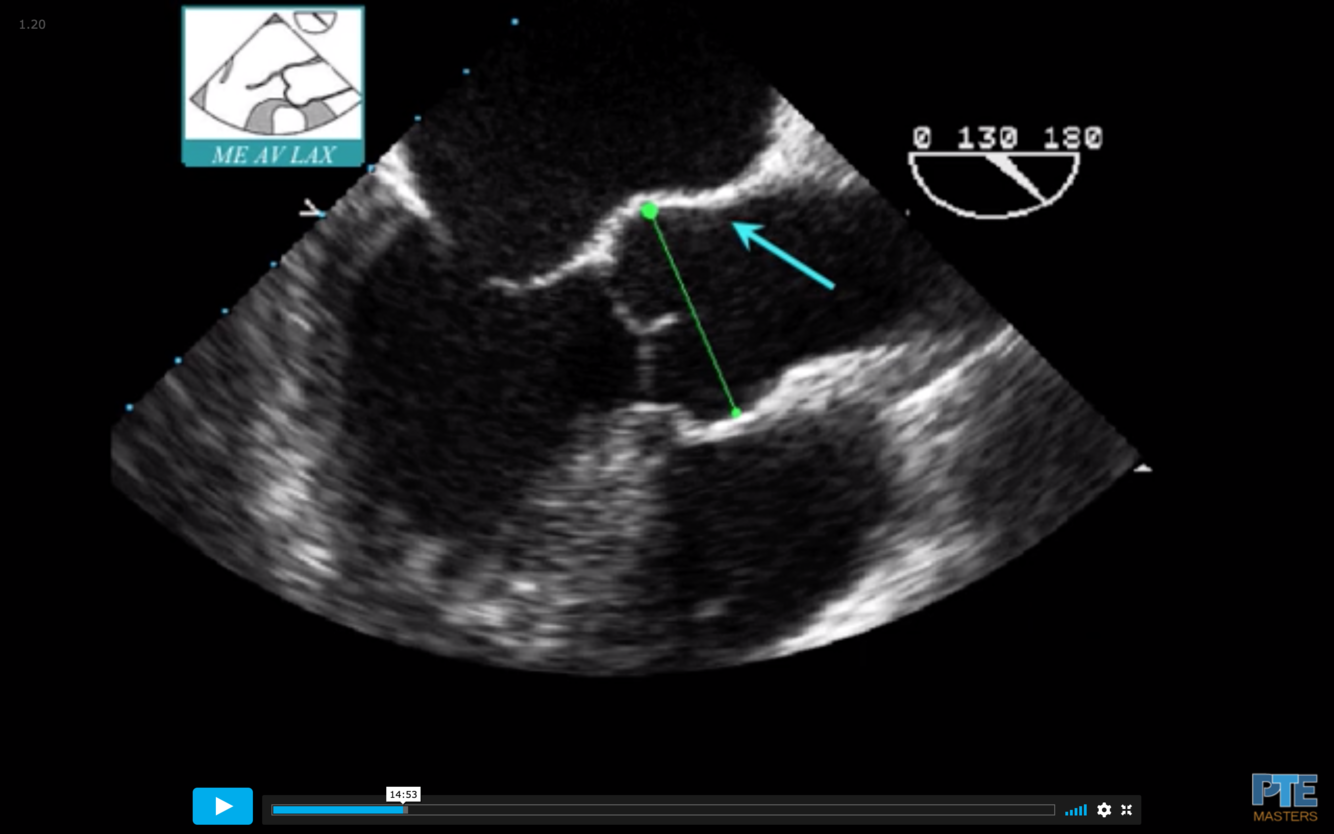

Find the ME AV LAX (120°)

Withdraw the probe to bring the right pulmonary artery in view

Decrease omniplane angle slightly by 10-20° to make the aortic wall symmetric